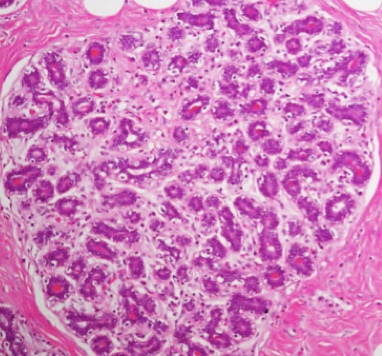

benign fibroadenoma

benign neoplasm of both the stromal and epithelial cell components of the breast. Well circumscribed, non infiltrative lesion that lacks atypia